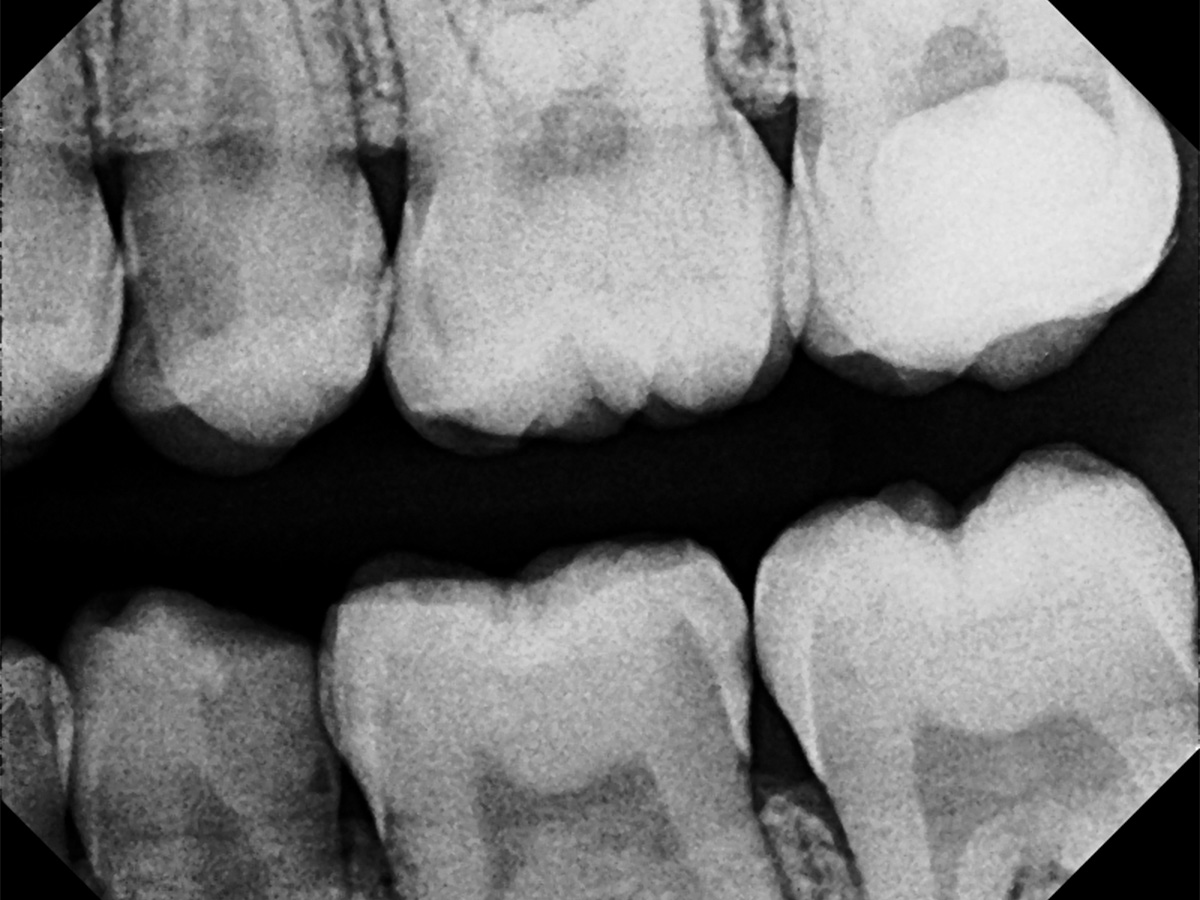

Abbildung 14

Recall: Aufnahme des Zahnes 25 fünf Monate nach Kappung.

Abbildung 15

Recall 25: Klinisches Bild nach fünf Monaten.